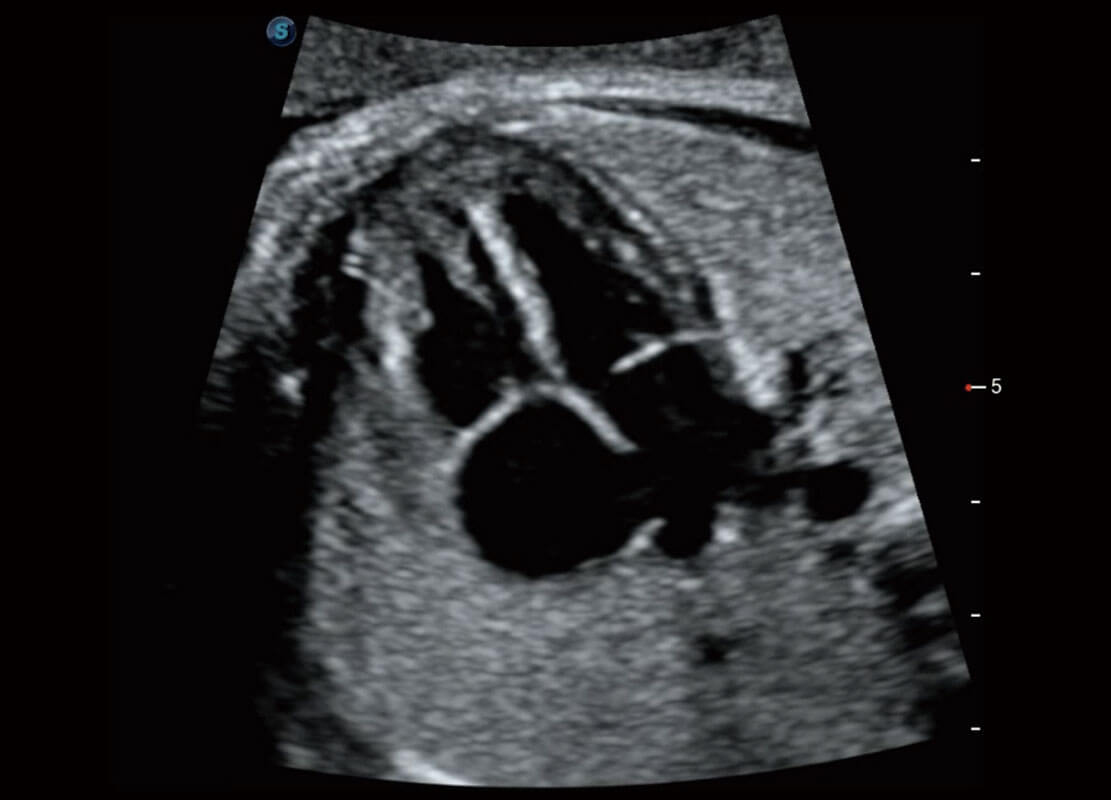

胎心筛查

P60搭载一系列胎儿心脏成像技术,实现精细的胎儿心脏评估。

• 四腔切面